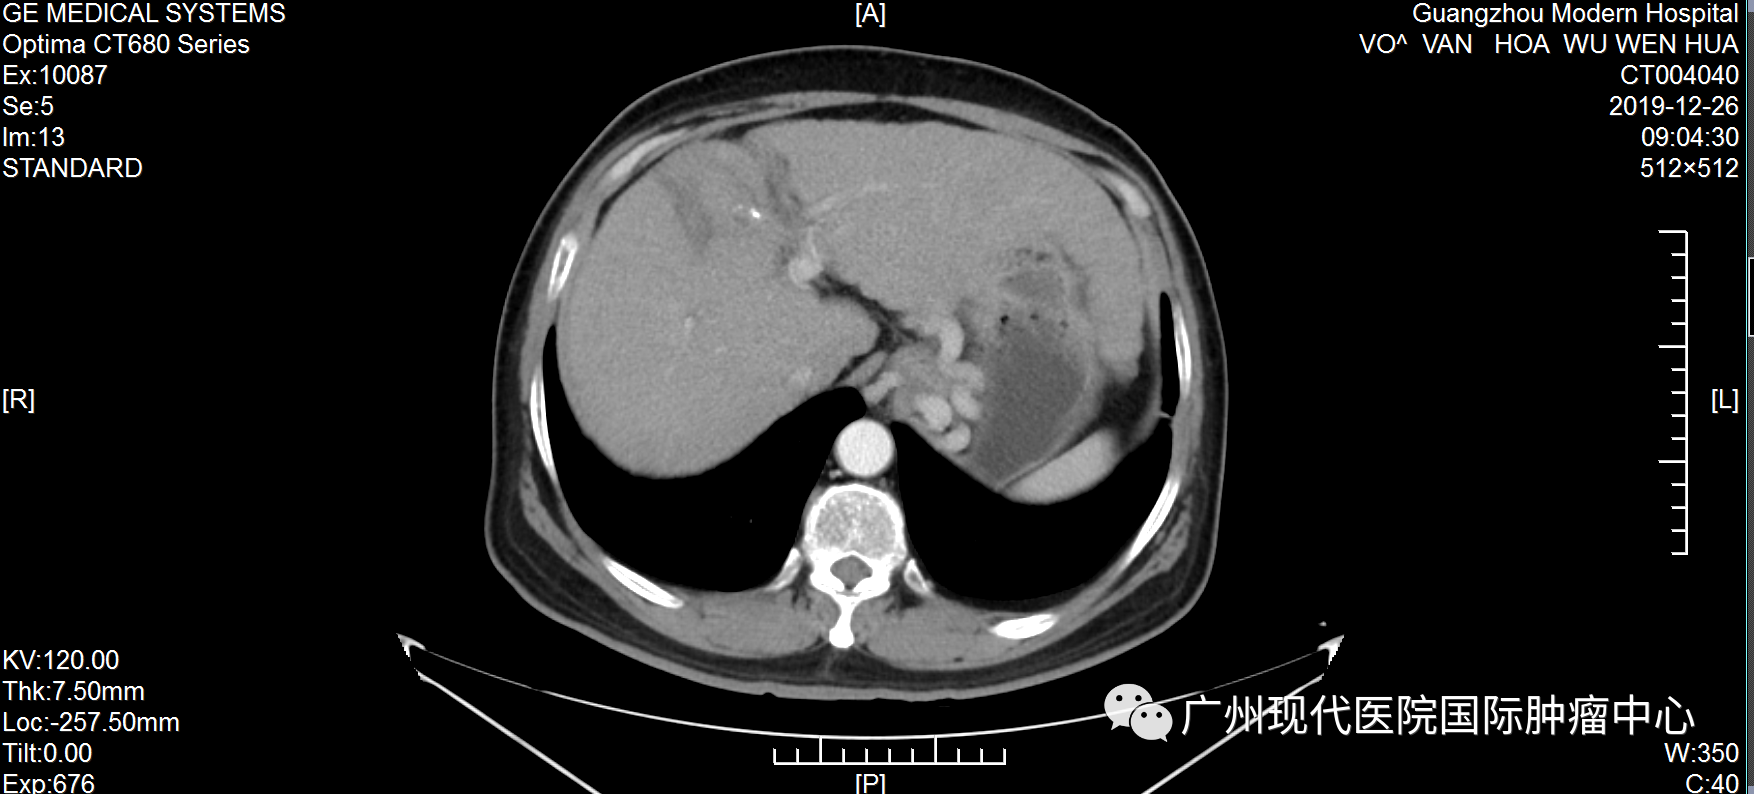

不愿做手术, 弟子推荐好医院 武文华自10岁起出家,年轻时,一直去各大佛寺学习佛教知识和游历,直至1999年时确诊丙肝,此后一直坚持吃药治疗。不曾想,时间的指针转到2019年,丙肝恶化为肝癌。 2019年6月,武文华因反复劳累出现低热,伴随右上腹胀痛、头痛等症状,且面部神经受影响,尤其是下颌与唇部麻痹且疼痛。随后,他到当地医院就诊,做腹部CT检查,初步诊断为肝细胞肝癌、肝硬化。当地医生建议做手术,武先生不愿意开膛破肚,也担心手术风险、术后感染等问题,于是拒绝越南医生的治疗方案。 武文华和妹妹及弟子合影 机缘巧合下,武文华的弟子了解到自己的一位亲友在一家口碑很好的癌症专科医院——圣丹福广州现代肿瘤医院获得了很好的治疗,现在肿瘤已经完全消失了。弟子把这家医院推荐给武文华,告诉他不用开刀也能很好地治疗癌症,并给他介绍最新的微创技术。“不用开刀”这一技术优势深深地吸引了武文华,他很快找到胡志明办事处咨询,并在工作人员的帮助下来到广州。 微创综合治疗, 让他重获新生 2019年7月,武文华来到圣丹福广州现代肿瘤医院。根据他的病情,医院MDT医疗团队研讨决定,给予他综合微创治疗方案。 第一次住院期间,武文华先后接受介入治疗、纳米刀等微创治疗。介入治疗可以切断癌细胞营养供给,抑制肿瘤生长,减少肿瘤转移,直至彻底杀死肿瘤;而纳米刀是一种全新的尖端肿瘤消融技术,通过电极探针释放高压脉冲击穿肿瘤细胞的细胞膜,形成多个纳米级不可逆的电穿孔,破坏细胞膜,从而破坏癌细胞组织,使细胞快速凋亡。他曾经的主治医生马主任表示,这个治疗方案,非常适合武文华这种不愿接受传统治疗、甚至对放化疗已经产生耐受性的癌症患者。 2019年武文华住院期间生活照 据了解,入院前,武文华体内的肿瘤大小为70*60mm。经介入栓塞治疗和纳米刀治疗后,肿瘤缩小到22*16mm。回忆治疗过程,武文华表示:“因为不需要开刀,每一次微创治疗都在半小时内结束。做介入治疗时,没有任何痛感,第二天就可以下床。纳米刀是在全麻的情况下做的,没什么感觉。” 治疗1个月后,肝部肿瘤明显缩小 治疗5个月后,肿瘤已基本消失 活动中,马主任回忆称:“他总共接受了5次介入治疗和纳米刀治疗,综合治疗完成后,肝部的肿瘤基本消失,他头痛发烧及面部神经影响等问题也得到了解决。”肿瘤消失后,为了巩固治疗效果,他遵守医嘱再次入院并接受了免疫治疗。 自2019年7月至今,武文华已经抗癌成功5年了,这对于他的家人而言是一种莫大的幸福。他的妹妹欣喜地说:“此前在越南的医院,医生下结论说他不做手术只能活3个月,如果做手术成功率只有30%。时间证明我们选择来广州治疗是对的,现在他每年仍然在越南定期检查,结果完全稳定,而健康的状态现在已经延长了5年,这是一个奇迹!” 医患情暖人心, 定下十年之约 这是武文华第三次回到医院。在采访中,他表示:“我完成治疗返回越南后,新冠疫情就爆发了,我像往常一样进行寺庙的日常管理工作,还积极参加抗疫的工作,我很幸运能够那么快地恢复健康,这要归功于医院的精心治疗和护理。” 住院期间,因为面部神经不适等症状,武文华被我院医护人员悉心照料照顾,他为之动容并为他们创作了一首诗:“别时合影它日忆,此处高风妙可夸。天使殷勤通昼夜,良医吐哺映莲花。”谈起写诗的初衷,他说:“我曾经在别的医院治疗过,后面依然选择这里,是因为这里的医生和护士都非常专业,对病人热情而周到。” 2019年,武文华出院时为我院赋诗及合影 活动中,武文华和主治医生马主任合影 他以亲身经历,对其他患者强调,肿瘤不是一种绝对导致死亡的疾病,而是一种慢性病。“现在我能够正常地饮食,工作,还能进行体育锻炼。如果你确诊了癌症,请不要灰心,不要悲伤,一定要遵守医嘱,相信自己可以恢复健康。” 抗癌明星的聚会中,马主任仔细聆听他的分享,不断绽放出感动与欣慰交织的笑容。她难掩心潮澎湃,还定下一场“十年之约”:“看到武大师目前拥有这么健康的状态,我感到我们医护人员所有的努力和付出都是值得的。希望十年后和大家再相聚!” 活动后,武文华还同其他抗癌明星们一起,体验了一场精彩纷呈的广州之旅。他们夜游珠江,体验现代都市的繁华;结伴同游宝墨园,观中华文化的博大精深。他们的癌后余生,正如脚下的路,徐徐绵延向前,充满阳光! 微创治疗技术简介 纳米刀:是一种全新的肿瘤消融技术,源于不可逆电穿孔技术,通过电极探针释放高压脉冲击穿肿瘤细胞的细胞膜,形成多个纳米级不可逆电穿孔,破坏细胞内外平衡,使细胞快速凋亡。治疗优势是时间短、 治疗区域的血管、神经等重要组织得以保留、安全可靠等。 1、具备创伤小、并发症少、安全、恢复快的优势。 2、可适应更多复杂的病情,包括胰腺、肝、肺、肾、前列腺以及其他实体肿瘤 介入治疗:在医学影像设备引导下穿刺,利用特制导丝等精密器械,将比静脉点滴药物浓度高2~8倍的抗肿瘤药物直接注入肿瘤内部,同时对肿瘤的供血动脉进行栓塞,实现肿瘤缩小甚至消失的目的。 1、具备创伤小、并发症少、安全、恢复快的优势。 2、适合采用传统放化疗效果不佳、不愿或不适合做手术等情况的患者。